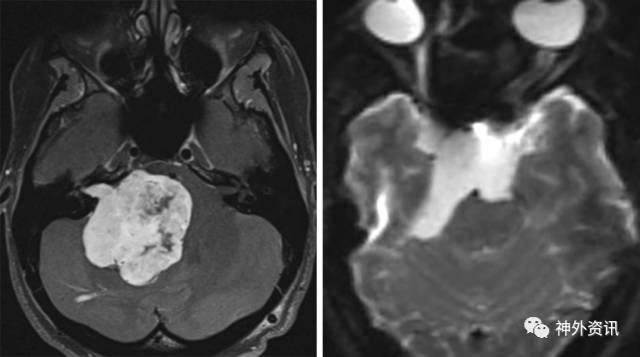

图1. 巨大的前庭神经鞘瘤(左)和脑干腹侧的表皮样囊肿(右)皆可通过扩大乙状窦后入路切除。